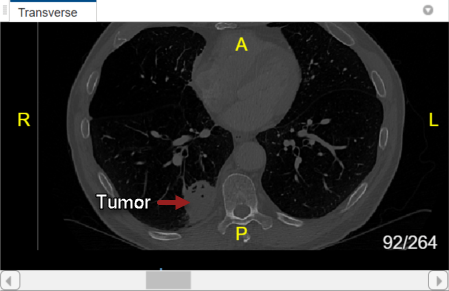

With lung_027.nii.gz selected in the Data Browser pane, explore the chest volume to identify the tumor region you want to label. The tumor is visible between slices 79 and 105 in the Transverse slice pane.